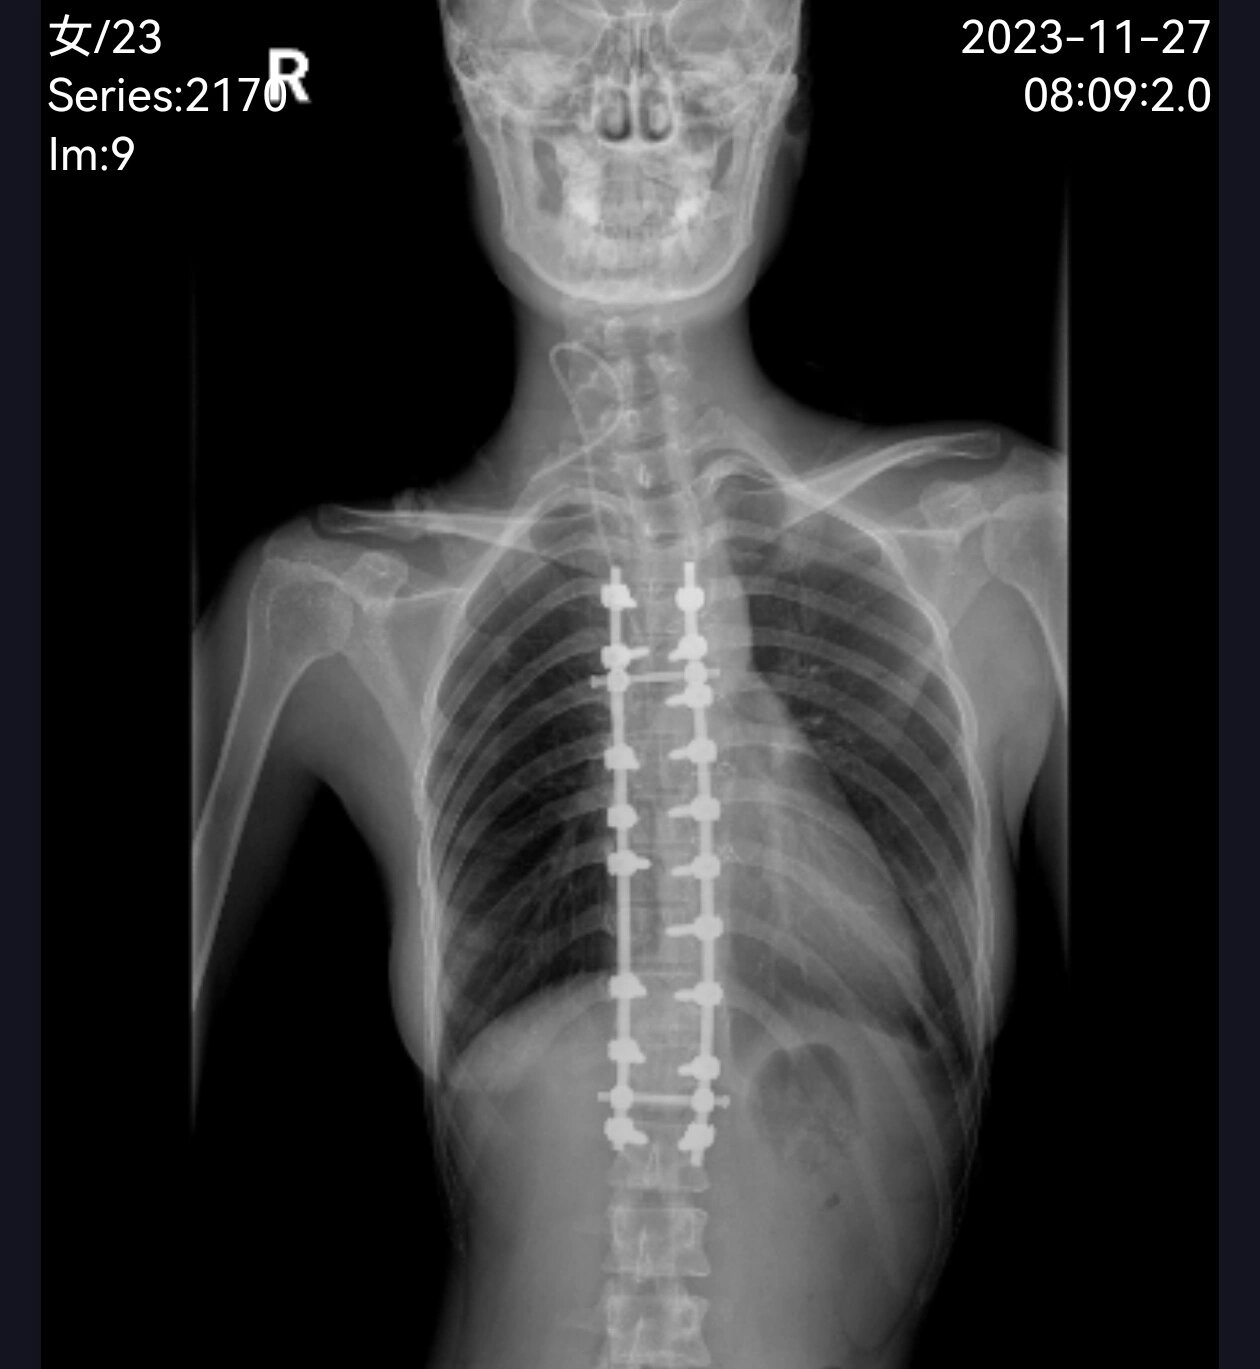

脊柱侧弯手术后

脊柱侧弯手术第八天 术后第八天 妹妹用尽全力去拍片子 我还担心得不